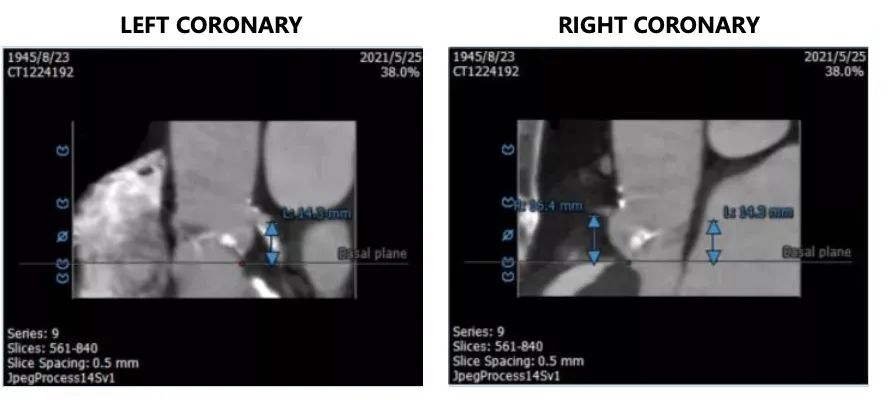

2. 左冠开口高度14.3mm,右冠开口高度16.4mm,高度可,根据瓦氏窦内径和瓣叶长度综合判断,冠脉堵塞风险小,双侧冠脉钙化严重。

左冠开口高度18.8mm,右冠开口高度21.9mm,高度可,根据瓦氏窦内径和瓣叶长度综合判断,冠脉堵塞风险小。